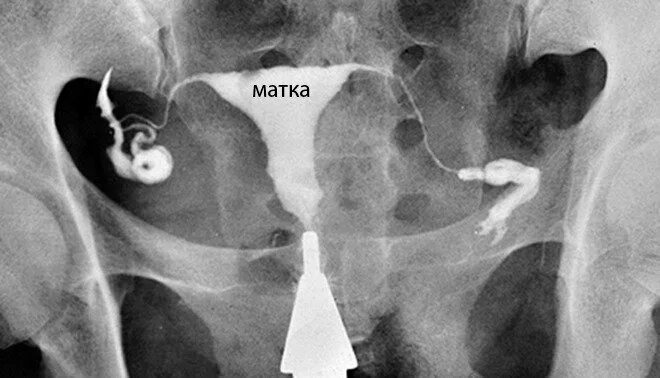

Проходимость маточных труб под наркозом